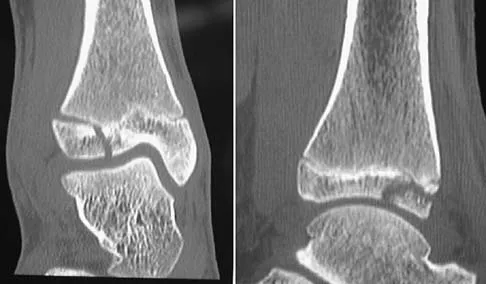

Question 88

A 13-year-old girl injures her ankle playing soccer. Radiographs reveal a displaced Tillaux fracture. CT scans are shown in Figure 25. What is the most important consideration for appropriate management?

Explanation